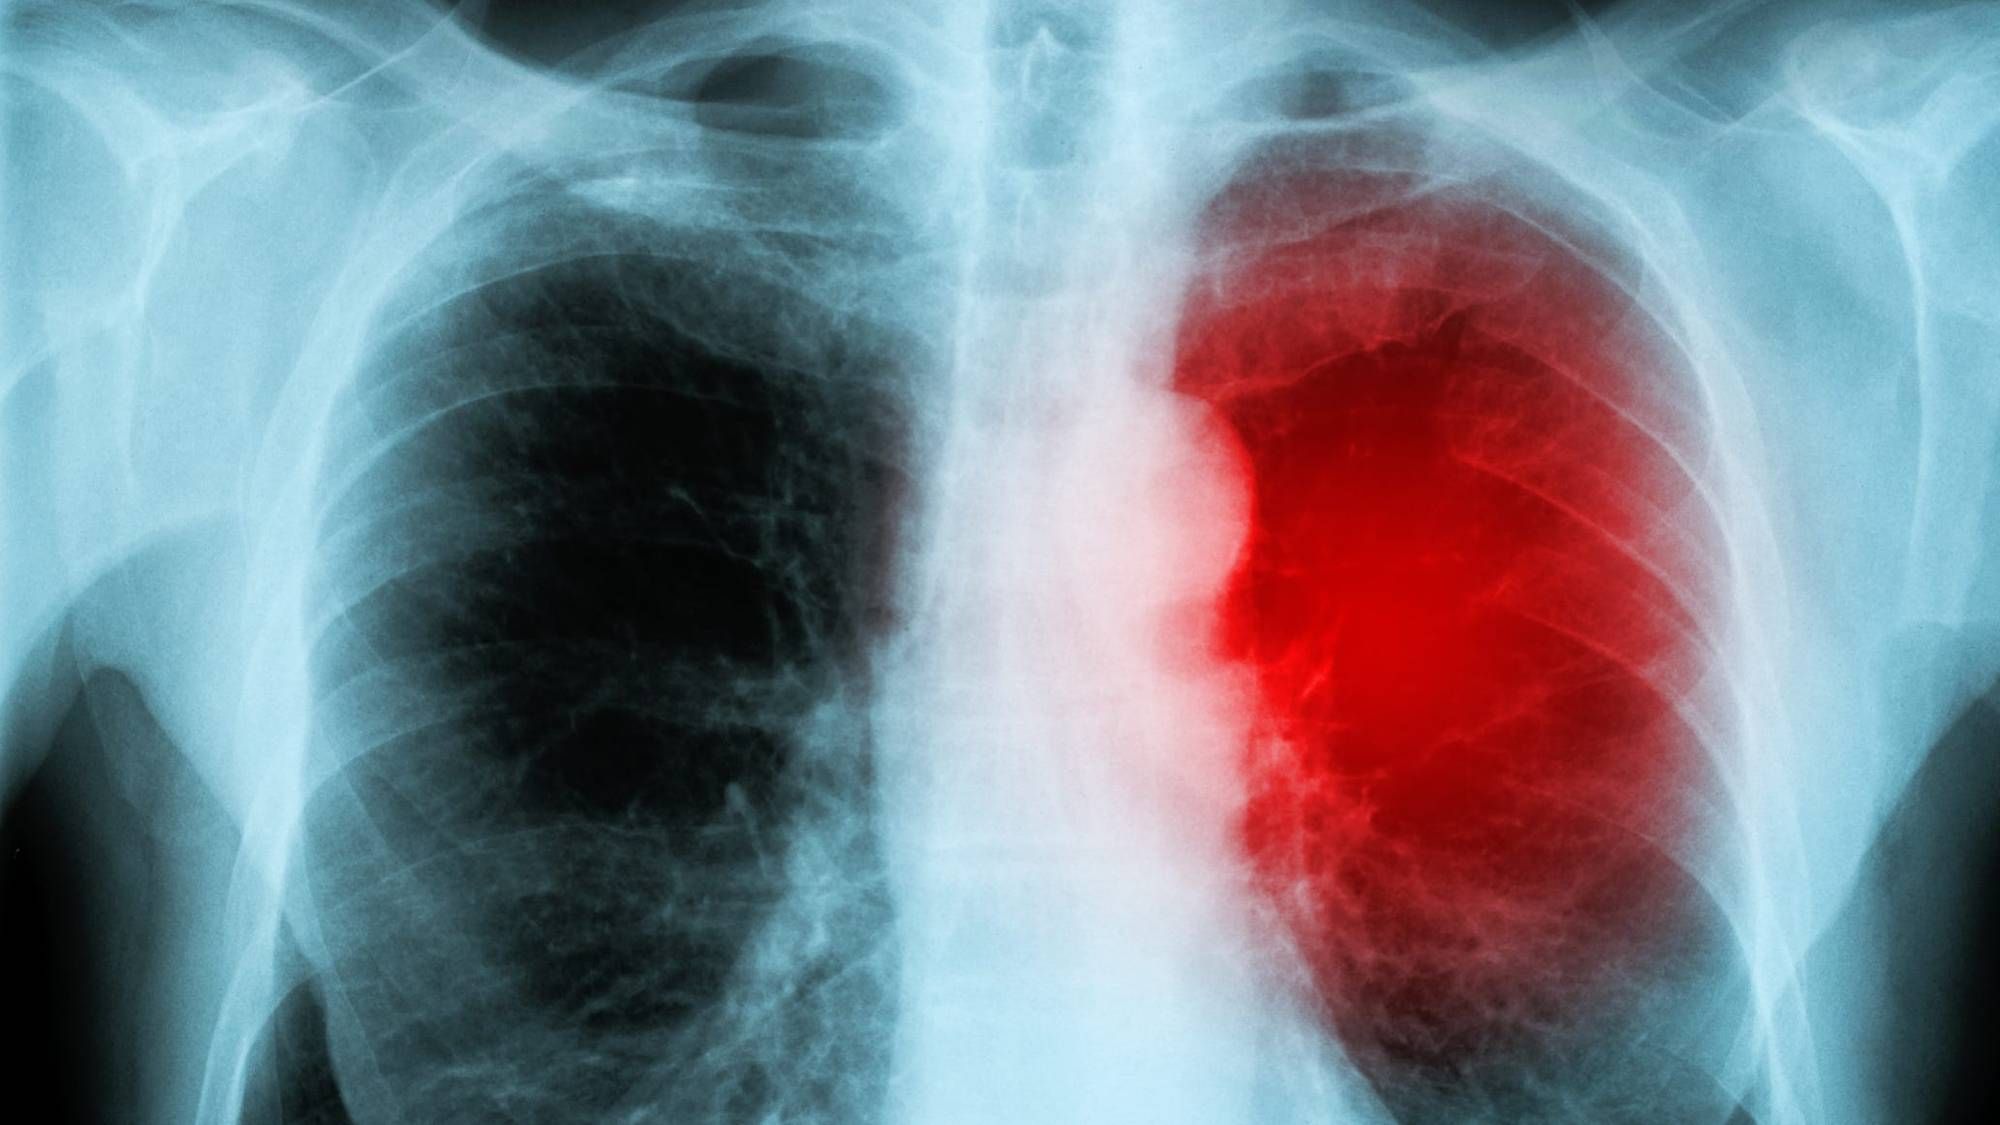

Doctors performed an EKG and discovered she had myocarditis, which is the inflammation of the heart muscle and can cause irregular heart beats, heart failure and sudden death.